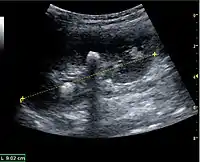

Figure 5. Simple renal cyst with posterior enhancement in an adult kidney. Measurement of kidney length on the US image is illustrated by '+' and a dashed line.[1]

Figure 6. Complex cyst with thickened walls and membranes in the lower pole of an adult kidney. Measurements of kidney length and the complex cyst on the US image are illustrated by '+' and dashed lines.[1]